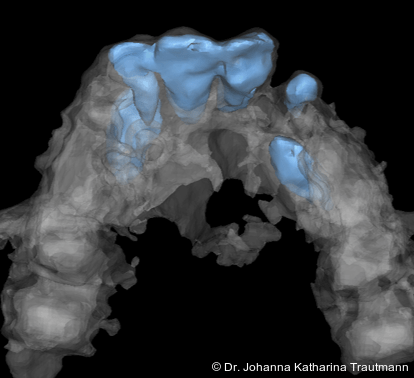

Zur genaueren Diagnostik der Lage beziehungen der Eckzähne und des Knochenangebotes im Spaltbereich kann neben den kieferorthopädi schen diagnostischen Unterlagen laut der S2 kLeitlinie Dentale digitale Volumentomografie6 auf eine dreidimensionale Bild gebung zurückgegriffen werden. In dieser zeigte sich eine vestibuläre Verlagerung des 13, eine palatinale Verlagerung des 23, sowie ein deutliches Knochendefizit im Spaltbereich mesial des hypoplastischen 22 (Abb. 2). Nach Auswertung der 3D-Daten erschien aufgrund der palatinalen Lage des 23 eine invasive Operation wie eine sekundäre Osteoplastik keinen entscheidenden Vorteil für die weitere Be handlung zu haben. In Rücksprache mit der Mund-Kiefer-Gesichtschirurgie der UMG wurde daher auf die OP verzichtet und initial die kieferorthopädische Therapie in den Vordergrund gestellt.